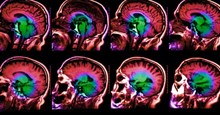

Và những người mắc bệnh này thường được chẩn đoán qua công nghệ đo điện não, chụp MRI, sinh thiết não, hoặc lấy mẫu dịch não tủy... Tuy nhiên, một phá hiện mới đến từ Hội đồng Nghiên cứu Y khoa Anh quốc cho rằng, xét nghiệm nước tiểu cũng là một trong những cách để chẩn đoán căn bệnh chết người này.